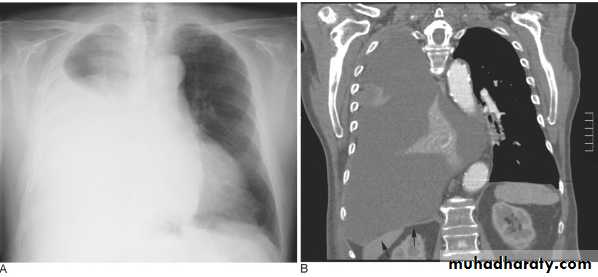

Massive pleural effusion with mediastinal shift to the left.

(A) Chest radiograph

(B) CT coronal reconstruction. A massive effusion displaces the mediastinum to the left. CT shows the important pleural effusion together with the enhanced atelectatic left lung.

Note also the depression of the right hemidiaphragm (arrows).